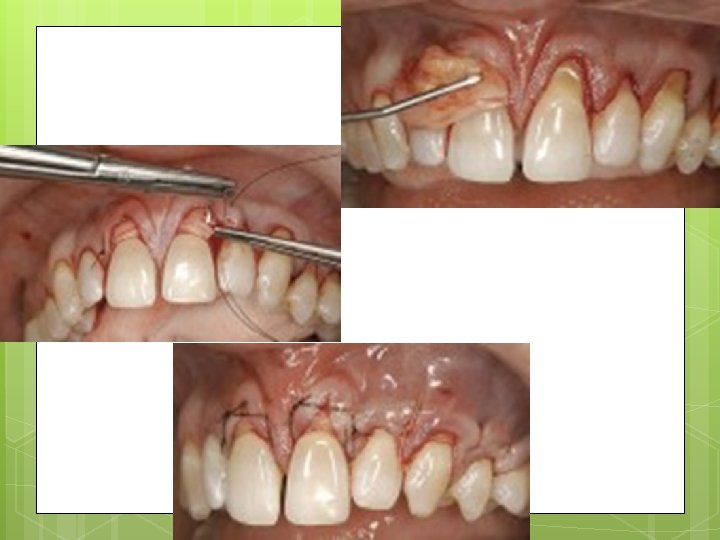

Modified Widman flap

. : 3. Flap retraction

Root planing with direct vision… THE MOST IMPORTANT STEP IN SURGICAL PROCEDURE 5 -Direct root planning

Surgical Procedure of tunnel flap: sulcular incisions on the labial and buccal only were performed with scalpel No. 15 blade to begin the partial-thickness dissection. The splitthickness dissection then was extended until continuity was established between all the recession sites without raising the papillae